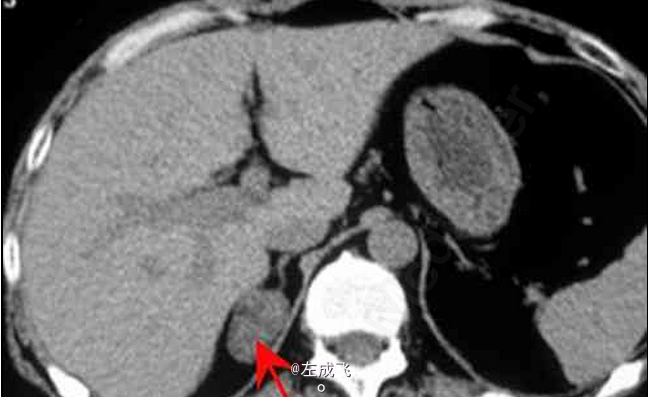

患者体检时偶尔发现右肾上腺区肿块,无其他明显症状 辅查CT,平扫示右肾上腺类圆形肿块,边界清楚;增强扫描呈不均匀强化